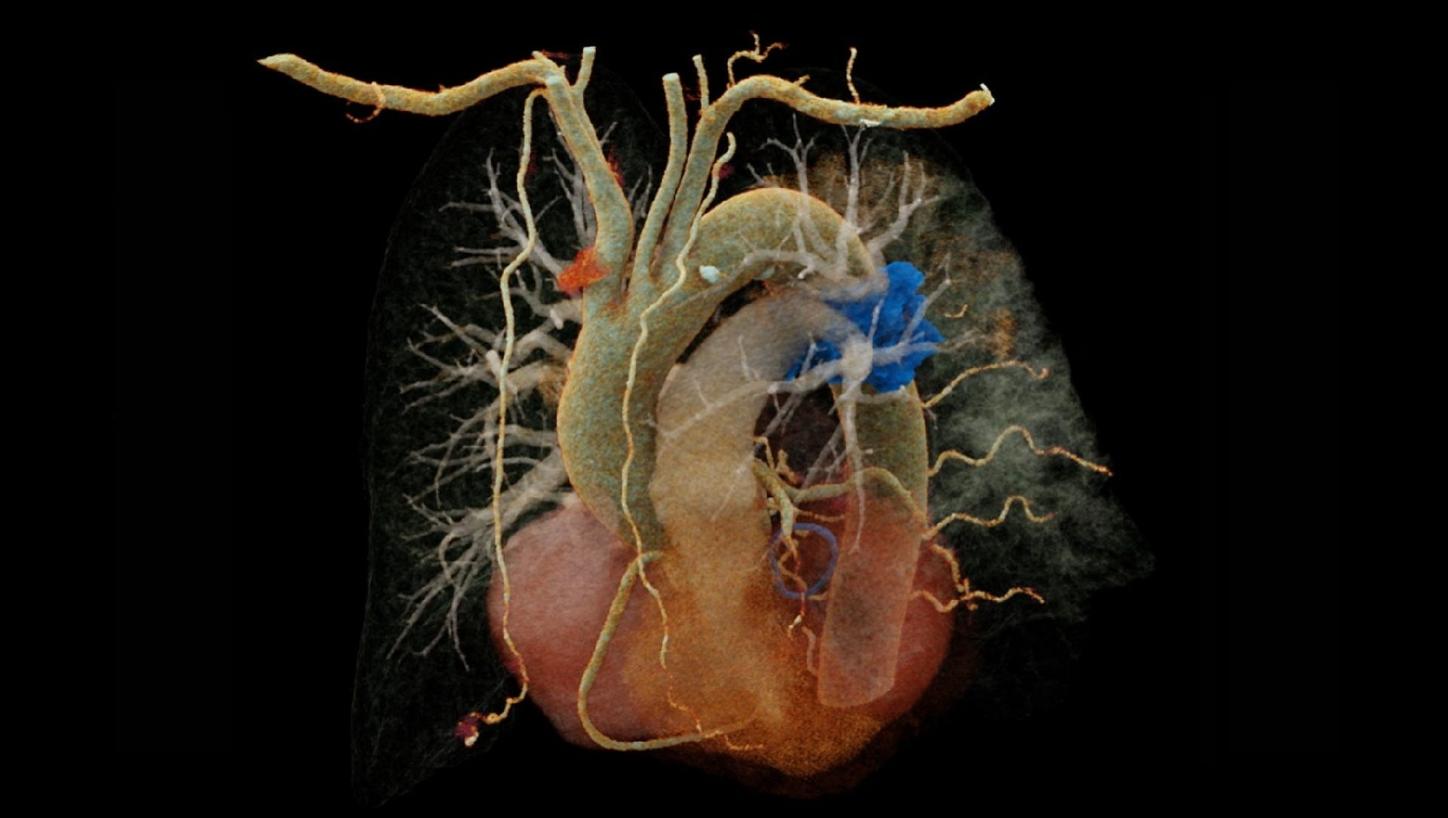

Fig. 2: Coronal maximum intensity projection (MIP) image of the pulmonary vasculature (a) demonstrates a filling defect in the lower part of the left pulmonary artery. Volume rendering technique (VRT) reconstructions (b, c) depict the pulmonary vessel arborization: In (b), a cross-sectional view, the filling defect is visible in the left pulmonary artery (arrow). In (c), an oblique view, the embolus is highlighted in blue, while the consolidations in the lung can also be appreciated (small arrows).

In this case, the targeted chest CTA enabled the use of a TRO-CT equivalent methodology. Therefore, the entire thoracic aorta was included in the scan range and timing was set to achieve optimal enhancement in the aorta and pulmonary arteries. Due to the high spatial resolution of the photon-counting detector, the coronary arteries could also be accurately evaluated.

The fine spatial detail (0.4 mm slice thickness) enabled an accurate evaluation of the coronary arteries to rule out severe CAD (as part of the differential diagnosis of chest pain) (see Figure 1). The use of advanced image reconstruction algorithms, such as ZeeFree, combined with the preview series function, resulted in only minor motion artifacts on the acquired scans, despite the high heart rate variability (Minimum: 86, Maximum: 158, average: 110). Detector-based quantum spectral imaging capabilities (lung analysis reconstruction) made it impressively fast to detect lung perfusion deficits caused by the PE and aided further therapy decision-making by down-grading disease severity. A fair dose length product (636 mGy*cm) was achieved during the chest CTA, utilizing the NAEOTOM Alpha.Prime CT scanner with an optimized protocol, serving as a true “one-stop-shop” TRO-CT examination.